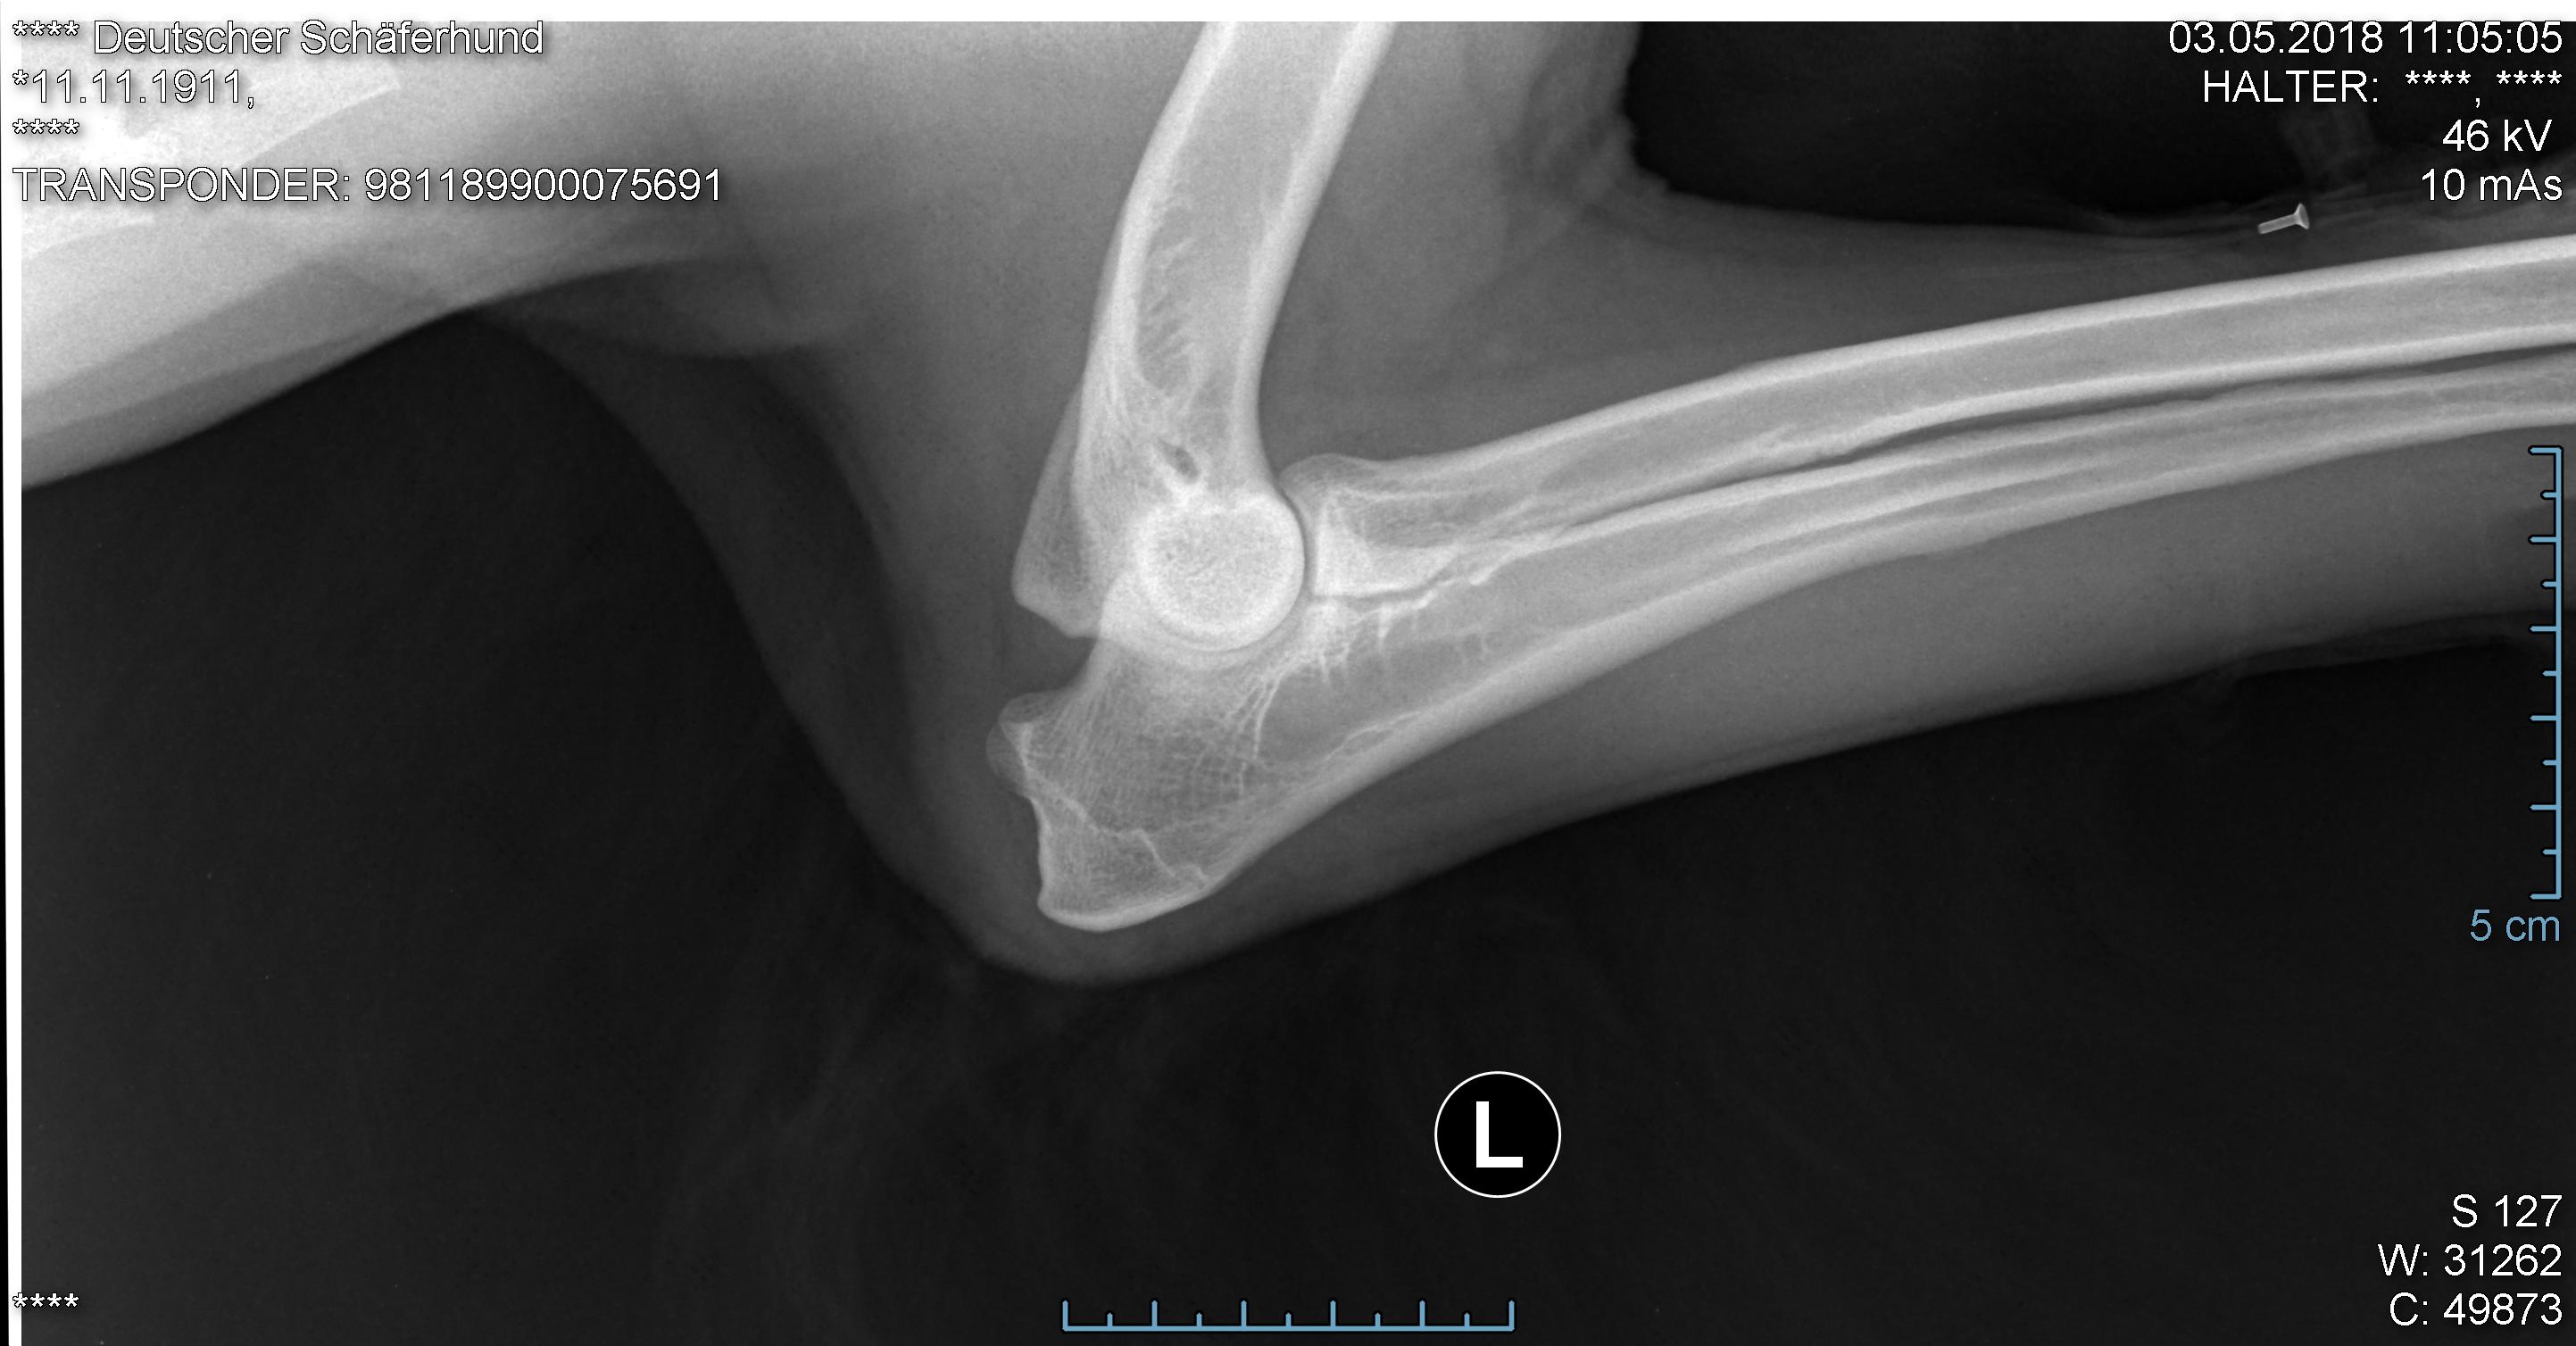

Ellbogen

Foto von Diego`s Hüfte